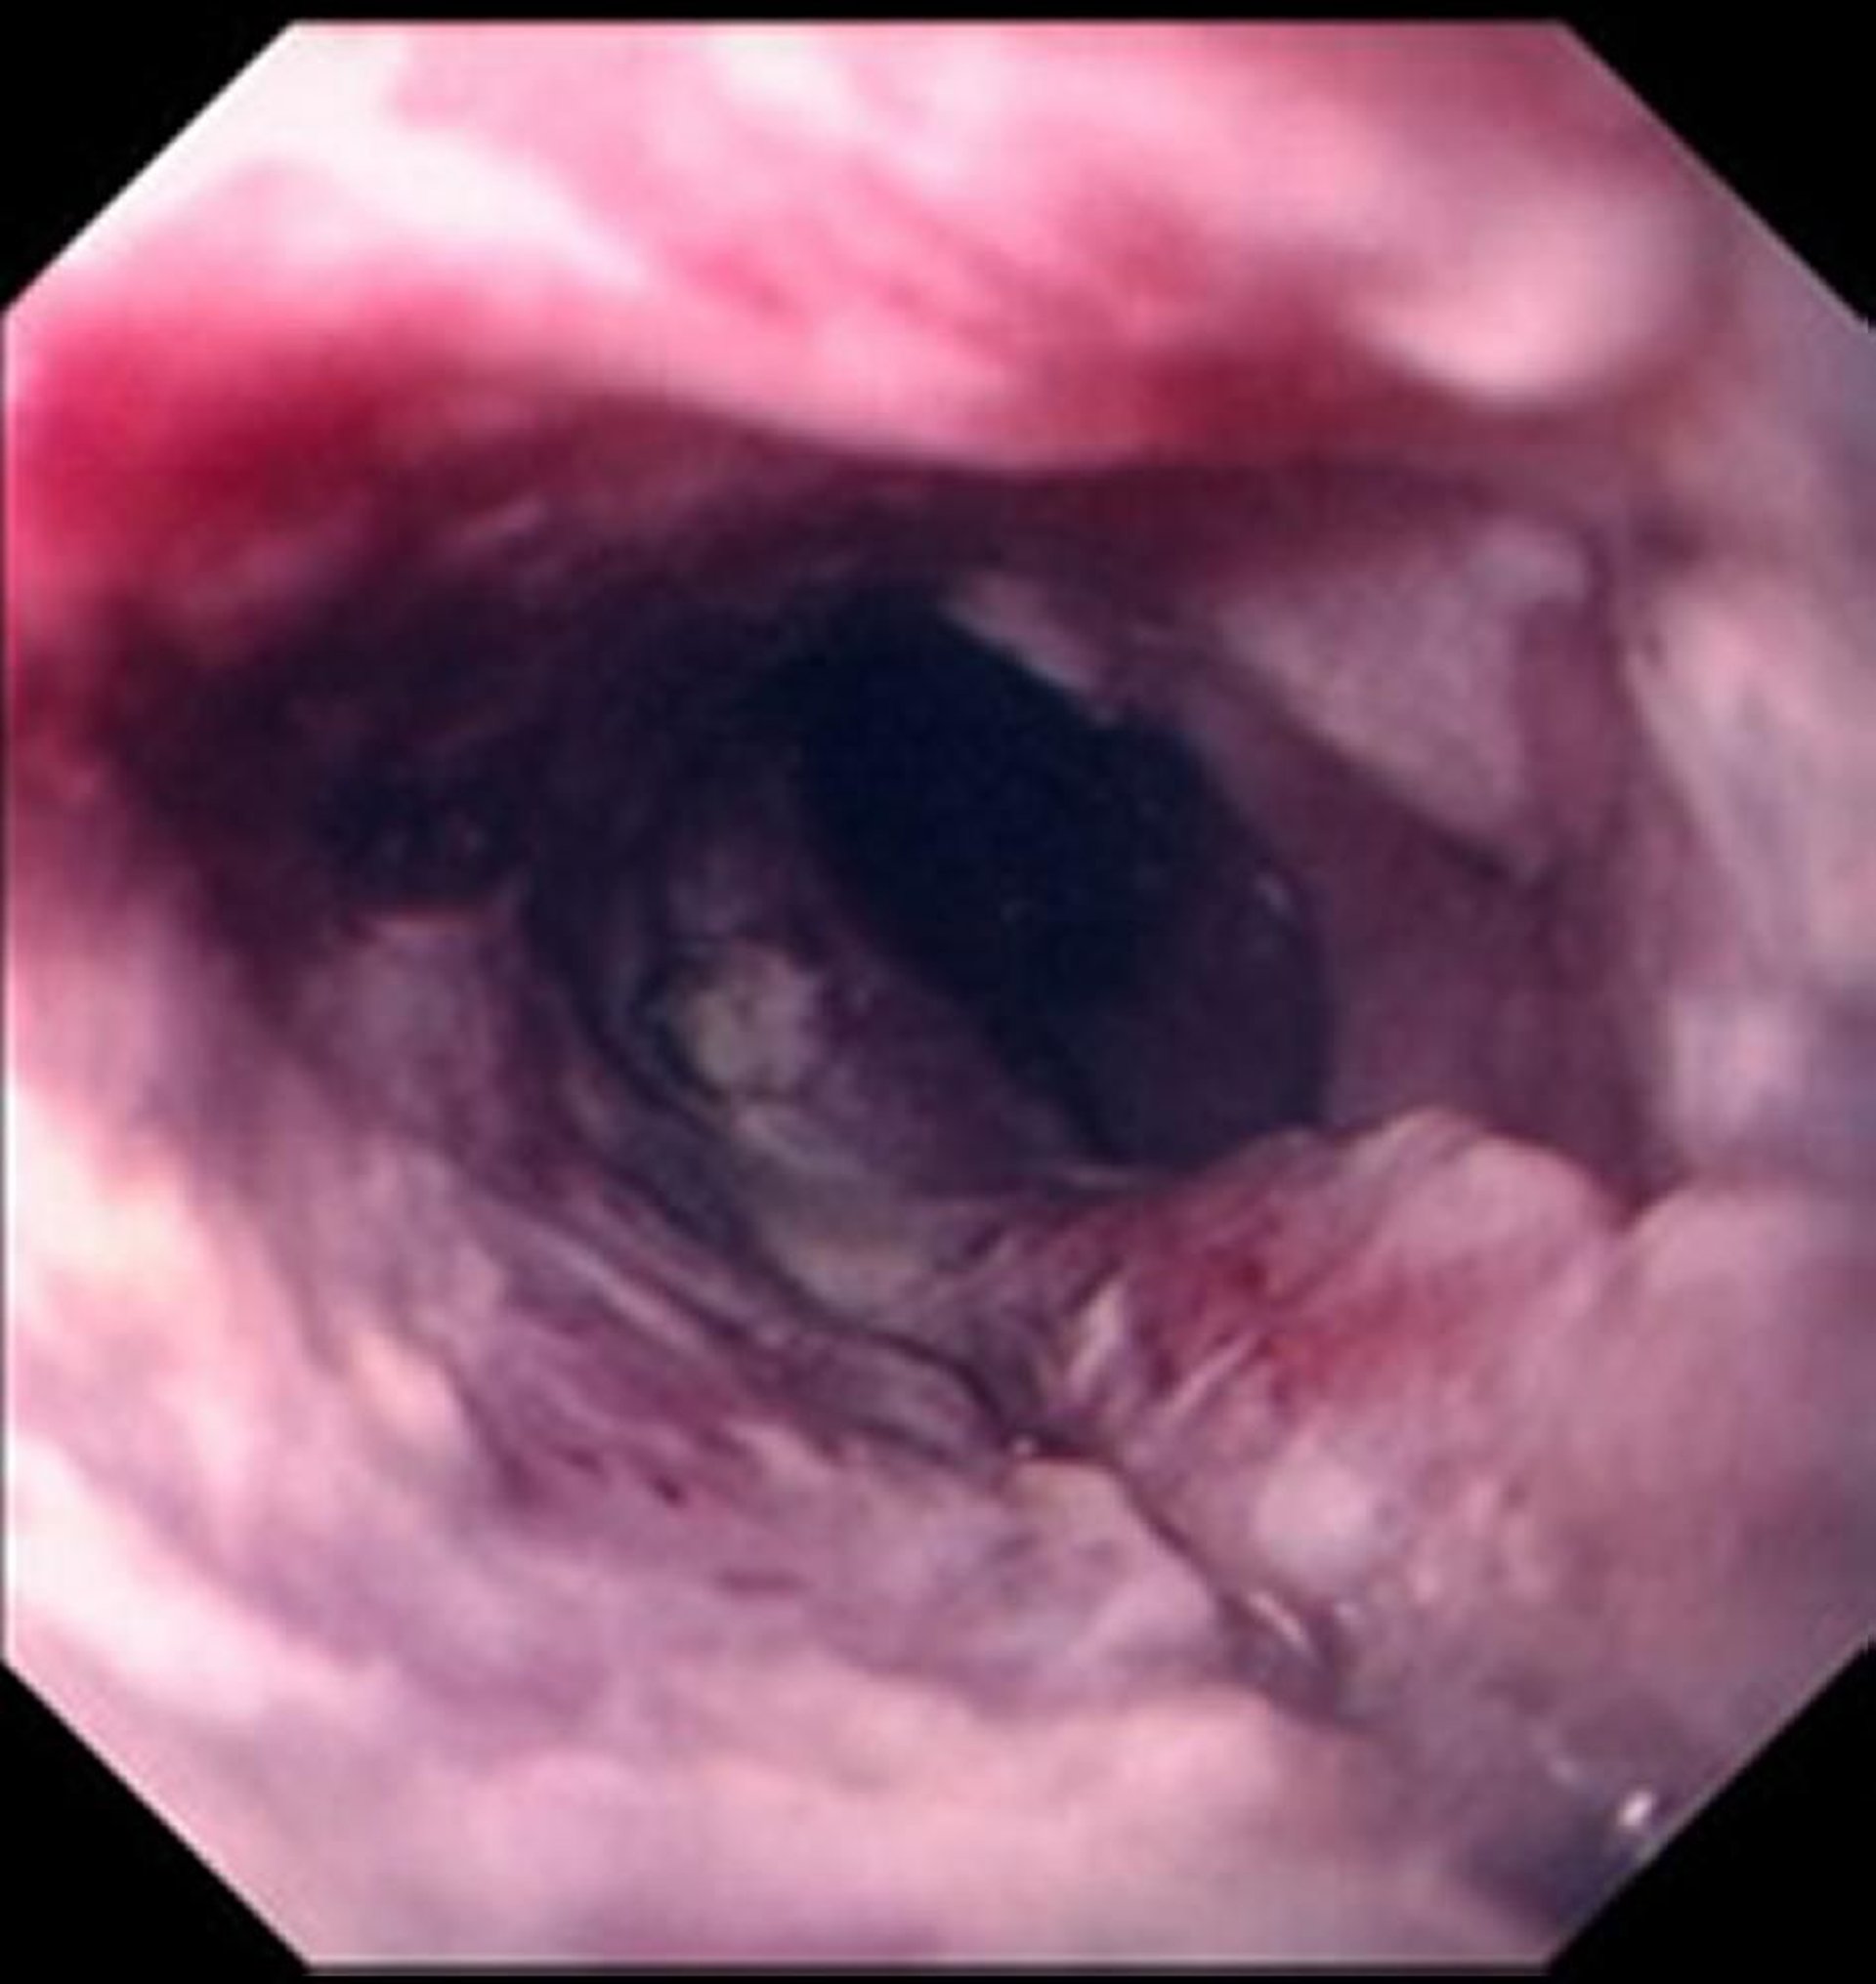

Carcinoma squamocellulare dell'esofago

Il carcinoma squamocellulare si manifesta tipicamente come una massa ulcerata che compromette il lume dell'esofago.

Images provided by David M. Martin, MD.